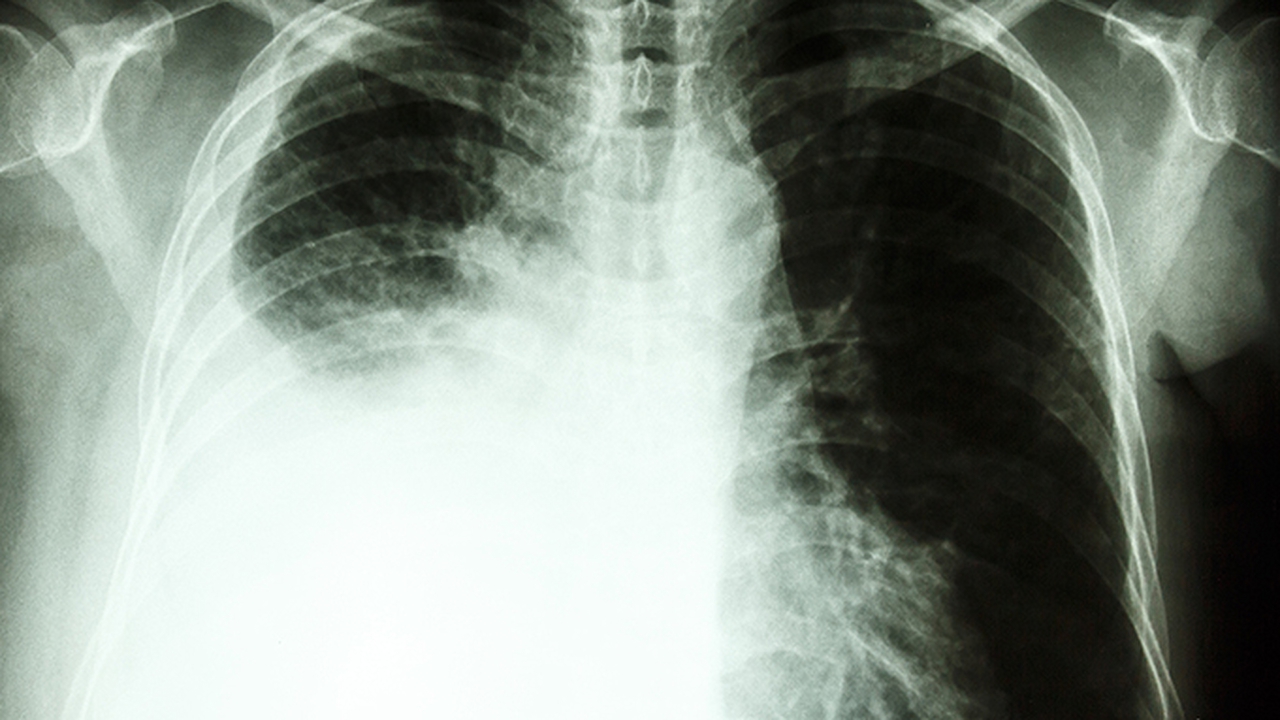

肺病是呼吸系统常见疾病,主要包括慢性阻塞性肺疾病、哮喘、肺炎、肺结核等。这些疾病多与环境因素、感染、遗传等有关,严重影响患者生活质量。及时就医选择专业医院对疾病控制至关重要。